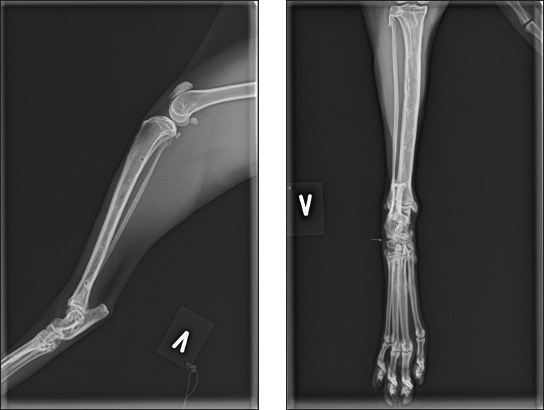

Fig. 2. (A and B) Mediolateral and craniocaudal digital radiograph of the left hock joint eight weeks post-operative. The fracture line was well visible. The lateral frame was removed at this stage. A protective bandage was applied to the external fixators to protect the cat and the environment (owner, kids, and furniture). Post-operative orthogonal radiographs were taken to confirm satisfactory reduction and pin placements. The cat was hospitalized for another 24 hours for analgesic treatment, where Methadone was gradually changed to Buprenorphine 0.3 mg/ml with a dose of 10–20 µg/kg (IM) at an interval of 8 hours (Bupaq vet. Bupaq Multidose vet. VetViva Richter, Salfarm Scandinavia AS). Additionally, the cat received a meloxicam oral mixture (suspension) of 0.5 mg/ml with a dose of 0.05 mg/kg (Metacam vet. Boehringer Ingelheim Animal Health Nordics A/S); oral meloxicam was continued at home for 7 days. Based on previous reports, we estimated a fracture healing time to be approximately 10–14 weeks (McCartney and Carmichael, 2000). Furthermore, advice was given to keep the cat in a large dog transport cage for 6 weeks. The cage should be large enough for food and water, bowels, toilet, and sleeping area, and the cat should be able to move around. The cat was allowed out for cuddles when the owner was home. After 6 weeks, the cat could be in the living room until the first scheduled re-examination at 8 weeks postoperatively. Complications arose after 7 days when the cat had escaped the owner, resulting in one loose pin on the craniolateral frame. The cat was anesthetized as previously, and orthogonal radiographs confirmed that the fracture was not affected. The cat was aseptically prepared and taken to the theatre, where the loos pin was replaced and the frame reconnected. A new bandage was provided before new orthogonal post-operative radiographs confirming proper pin placement. The cat was discharged the same day, and the initial post-operative plan was maintained. Eight weeks postoperatively, the cat was back for re-examination and radiographs. The owner reported that the cat moved freely around the house after 6 weeks of cage rest. The cat was anesthetized as previously, orthogonal radiographs revealed good fracture healing (Fig. 2a and 2b), and the lateral frame was removed according to standard procedures (Kraus et al., 2003). Twelve weeks postoperatively, the cat was back for re-examination and radiographs, and the owner could report that the cat was doing fine. The cat was anesthetized as previously for orthogonal radiographs, which revealed good fracture healing, and the medial frame was removed. A set of new orthogonal radiographs was taken after frame removal. Palpation of the affected talocrural joint revealed a moderately reduced range of motion (ROM) compared to the opposite joint. Measurements with a goniometer showed left extension at 160°, flexion at 67°, right extension at 167°, and flexion at 20° (Jaeger et al., 2007). Thirty-three weeks postoperatively, the cat was seen for a progress check. The cat was still not allowed outdoors. Slight lameness was evident when the cat moved freely on the floor. There was no pain or swelling in the affected area during palpation, and the ROM had improved, but it was still reduced compared to the opposite limb (left extension 163° and flexion 30°). The cat was anesthetized as previously for orthogonal radiographs (Fig. 3a and 3b). DiscussionTo the authors’ knowledge, this is the first reported “Hawkins type 3” talar neck fracture in a cat. Hawkins initially described talar neck fracture in humans based on initial fracture displacement: type I indicates a nondisplaced fracture; type II, a displaced subtalar joint (subluxated or dislocated); and type III, a dislocated tibiotalar joint (Hawkins LG, 1970), which was later modified by Canale and Kelly (1978) and Vallier et al. (2014). There is currently no classification scheme for talar fractures in small animals, probably due to their rarity. So far, cat talar neck fractures have been reported as minimally displaced or with luxation of the talar head (DeCamp et al., 2016). Reported treatment options for talar neck fractures include casts for non-displaced fractures, counter sunken pins and lag screws protected with a lateral splint or an external fixator, or solely by external fixators (Denny, 1993; McCartney and Carmichael, 2000; DeCamp et al., 2016).

Fig. 3. (A and B) Mediolateral and craniocaudal digital radiographs of the left hock joint. The fracture line is still evident. The yellow straight arrow points to the lateral calcaneoquartal joint, where a lack of bone is observed, believed to be due to a loose pin related to complications after the cat escaped the owner. Nevertheless, there was no pain or instability during palpation. This area can also be seen in Figure 2. The area appears larger in Figure 3b, likely due to slight angulation differences between the two radiographs. Considering Halsted’s principles of surgery, special attention was given to the soft tissue, particularly the vasculature and collateral support, when planning this surgery (Cushing, 1922). Due to the nature of the fracture in this cat, assessing the state of the collateral support was difficult. However, disruption was anticipated, so a type 1b external fixator was chosen, as loss of collateral stability in the tarsocrural joint in cats has been successfully treated with external fixators (Kulendra et al., 2011; Jaeger et al., 2005). Although the initial plan was a closed reduction, this was converted to a minimally invasive approach. In humans, Hawkins type 3 fracture is typically treated with open surgery and internal fixations (Buza and Leucht, 2018). In this instance, the decision was made to reject the lag screw due to concerns that motion between the talus and calcaneus could potentially lead to either a fractured screw or loosening (McCartney and Carmichael, 2000). One previous case series of five cats with talar neck fractures did not encounter any complications, utilizing only an external fixator in four of the cats (McCartney and Carmichael, 2000). In this case, complications were encountered; the pin, which came loose after the cat escaped the owner, was replaced and is not believed to have interfered with the outcome. Furthermore, the reduced ROM could result from the prolonged immobilization of the joint. Prolonged immobilization of joints is considered detrimental and predisposes to joint stiffness (Jurvelin et al., 1986; 1989; Haapala et al., 1999). Preliminary studies using hinged transarticular external fixators have shown promising results to hinder this process (Jaeger et al., 2005). As a result of various injuries and potential intra-articular damage from the initial injury, combined with prolonged joint immobilization, might be the combined cause of reduced ROM and potentially lead to arthritis (Fournier et al., 2012; Haverkort et al., 2015). Nonetheless, based on the last radiographs, there is no indication of the development of arthritis, meaning that joint mobility could improve as time progresses and the cat is outdoors. Avascular necrosis and post-traumatic arthritis are common complications of Hawkins type 3 talar neck fractures in humans (Fournier et al., 2012; Vallier et al., 2014; Haverkort et al., 2015; John A Buza and Leucht, 2018). In cats, the main blood supply to the talus comes from branches of the dorsal pedal artery, with an array of intraosseous and extraosseous anastomoses (Barnes, 1993). Previously, it was believed that humans shared a similar blood supply; however, recent studies have revealed that most of the blood supply in humans derives from the posterior tibial artery. This discovery might explain some inconsistencies in human treatment outcomes (Miller et al., 2011). In this case, as in previous published cases, the fracture cause was of unknown origin. However, all were closed fractures (McCartney and Carmichael, 2000), meaning that we can only speculate on the mechanism of the injury. In humans, it is considered that hyperdorsal flexion of the foot on the leg causes talar neck impingement against the anterior distal tibia, causing the fracture. If the force continuous, the talar body dislocates posterior medial and rotates around the medial collateral ligament (Peterson et al., 1976; Kapoor and Patra, 2011). Whether this mechanism applies to cats is unknown, yet it is a plausible theory based on pre-operative radiographs. ConclusionThis case adds to previous cases in cats with talar neck fractures, demonstrating that ESF provides fracture stability, preserves soft tissue, and is simple and well-tolerated. Additionally, the option for disabling the fixation and when the fracture has healed, there are no concerns for future implant issues. AcknowledgmentAniCura Jeløy Dyresykehus for the support. Conflict of interestThe author declares that there is no conflict of interest. Authors’ contributionJon Andre Berg was the single author of the case. FundingThis case report was privately funded. Data availabilityAll data supporting the findings of this study are available within the manuscript. ReferencesBarnes, J. 1993. Cardiovascular System, In: Hudson, L. and Hamilton, W. Eds., Atlas of Feline Anatomy for Veterinarians. Saunders, St. Louis, USA, pp: 103–105. Buza, J.A. and Leucht, P. 2018. Fractures of the talus: current concepts and new developments. Foot Ankle Surg. 24, 282–290. Canale, S.T. and Kelly, F.B.Jr. 1978. Fractures of the neck of the talus. Long-term evaluation of seventy-one cases. J. Bone Joint Surg. 60, 146–156. Carmichael, S. and Marshall, William.G. 2018. Tarsus ans Metatarsus, In: Veterinary Surgery Small Animals. Eds., Johnston, Spencer.A., Tobias and Karen.M. St. Louis, MO: Elsevier, pp: 1193–1209. Cook, J.L., Evans, R., Conzemius, M.G., Lascelles, B.D.X., McIlwraith, C.W., Pozzi, A., Clegg, P., Innes, J., Schulz, K., Houlton, J., Fortier, L., Cross, A.R., Hayashi, K., Kapatkin, A., Brown, D.C. and Stewart, A. 2010. Proposed definitions and criteria for reporting time frame, outcome, and complications for clinical orthopedic studies in veterinary medicine. Vet. Surg. 39, 905–908. Cushing, H. 1922. William Stewart Halsted, 1852-1922. Proceedings of the American Academy of Arts and Sciences, Washington, D.C., USA, 58, 599–604. DeCamp, Charles.E., Johnston, Spencer.A., Dejardin, Lóíc.M. and Schaefer, Susan.L. 2016. Fractures and other orthopaedic injuries of the Tarsus, Metatarsus and Phalanges, In: Brinker, Piermattei and Flo’s Handbook of Small Animal Orthopaedics and Fracture Repair. Ed., DeCamp, C.E Elsevier, St. Louis pp: 730–731. , Denny, H.R. 1993. The hind limb, in: A Guide to Canine and Feline Ortopaedic Surgery. Oxford, UK: Blackwell Scientific Publications, pp: 284–393. Fournier, A., Barba, N., Steiger, V., Lourdais, A., Frin, J.M., Williams, T., Falaise, V., Pineau, V., Salle de Chou, E., Noailles, T., Carvalhana, G., Ruhlmann, F. and Huten, D. 2012. Total talar fracture—Long-term results of internal fixation of talar fractures. A multicentric study of 114 cases. Orthop. Traumatol. Surg. Res. 98(4 Suppl), S48–55. Haapala, J., Arokoski, J.P.A., Hyttinen, M.M., Lammi, M., Tammi, M., Kovanen, V., Helminen, H.J. and Kiviranta, I. 1999. Remobilisation does not fully restore immobilisation induced articular cartilage atrophy. Clin. Orthop. Relat. Res. 362, 218–229. Haverkort, J.J.M., Leenen, L.P.H. and Wessem, K.J.P. van 2015. Diagnosis and treatment of talar dislocation fractures illustrated by 3 case reports and review of literature. Int. J. Surg. Case Rep. 16, 106–111. Hawkins, L.G. 1970. Fractures of the neck of the talus. J Bone Joint Surg Am 52, 991–1002. Jaeger, G., Marcellin-Little, D., DePuy, V. and Lascelles, B. 2007. Validity of goniometric joint measurements in cats. Am. J. Vet. Res. 68, 822–826. Jaeger, G.H., Wosar, M.A., Marcellin-Little, D.J. and Lascelles, B.D.X. 2005. Use of hinged transarticular external fixation for adjunctive joint stabilisation in dogs and cats: 14 cases (1999-2003). J. Am. Vet. Med. Assoc. 227, 586–591. Jurvelin, J., Kiviranta, I., Säämänen, A. -M, Tammi, M. and Helminen, H.J. 1989. Partial restoration of immobilisation-induced softening of canine articular cartilage after remobilisation of the knee (stifle) joint. J. Orthop. Res. 7, 352–358. Jurvelin, J., Kiviranta, I., Tammi, M. and Helminen, J.H. 1986. Softening of canine articular cartilage after immobilisation of the knee joint. Clin. Orthop. Relat. Res. 207, 246–252. Kapoor, S.K. and Patra, S.R. 2011. Talar neck fracture associated with talonavicular dislocation and fracture of posteromedial process of Talus. J. Foot Ankle Surg. 50, 758–761. Kraus, K.H., Toombs, J.P. and Ness, M.G. 2003. External fixation in small animal practice, 1st ed. J. Feline Med. Surg. Oxford, UK: Blackwell Science Ltd. Kulendra, E., Grierson, J., Okushima, S., Cariou, M. and House, A. 2011. Evaluation of the transarticular external skeletal fixator for the treatment of tarsocrural instability in 32 cats. Vet. Comp. Orthop. Traumatol. 24, 320–325. Lahunta, H.E. and A. de, Howard E. Evans, Lahunta, A. de 2013. Miller’s Anatomy of the Dog, 4th ed. St. Louis, MO: Elsever, Saunders. Lee, C., Brodke, D., Perdue, P.W. and Patel, T. 2020. Talus fractures: evaluation and treatment. J. Am. Acad. Orthop. Surg. 28, e878–e887. McCartney, W.T. and Carmichael, S. 2000. Talar neck fractures in five cats. J. Small Anim. Pract. 41, 204–206. Miller, A.N., Prasarn, M.L., Dyke, J.P., Helfet, D.L. and Lorich, D.G. 2011. Quantitative assessment of the vascularity of the Talus with gadolinium-enhanced magnetic resonance imaging. J. Bone Joint Surg. 93, 1116–1121. Palmer, R.H. 1999. Biological osteosynthesis. Vet. Clin. North Am. Small Anim. Pract. 29, 1171–1185. Peterson, L., Romanus, B. and Dahlberg, E. 1976. Fracture of the collum tali—an experimental study. J. Biomech. 9, 277–279. Piermattei, D., Flo, G. and DeCamp, C. 2006. Handbook of Small Animal Orthopedics and Fracture Repair, 4th ed. Saunders, Philadelphia, PA: Vallier, H.A., Reichard, S.G., Boyd, A.J. and Moore, T.A. 2014. A new look at the Hawkins classification for Talar neck fractures: which features of injury and treatment are predictive of osteonecrosis? J. Bone Joint Surg. 96, 192–197. Vollmerhausl, B., Roos, H., Matis, U., Blümp, U. and Fischer, H. 2002a. Zur klinisch-angewandten und funktionellen Anatomie des Sprunggelenks der Hauskatze. Teil 1: Tarsalskelett. Teil 1: Tarsalskelett. Tierärztl. Prax. 30, 131–137. Vollmerhausl, B., Roos, H., Matis, U., Blümp, U. and Fischer, H. 2002b. Zur klinisch-angewandten und funktionellen Anatomie des Sprunggelenks der Hauskatze. Teil 2: Gelenke, Bänder, Muskeln des Tarsus. Tierärztl. Prax. 30, 202–210. von Knoch, F., Reckord, U., von Knoch, M. and Sommer, C. 2007. Fracture of the lateral process of the talus in snowboarders. J. Bone Joint Surg. 89, 772–777. Young, R.P., Scott, S.H. and Loeb, G.E. 1993. The distal hindlimb musculature of the cat: multiaxis moment arms at the ankle joint. Exp. Brain Res. 96, 141–151. | ||